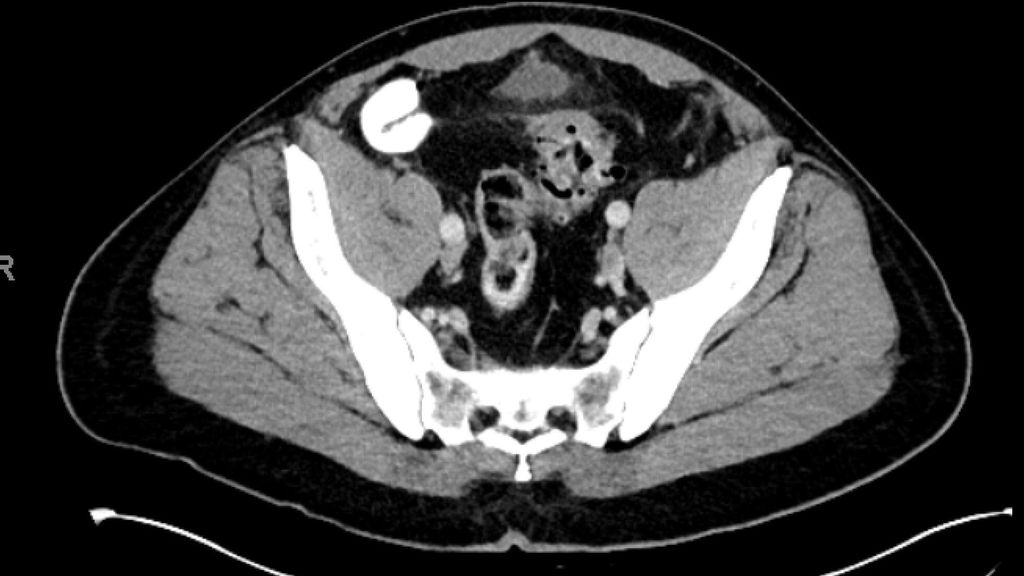

diverticulite compliquée aiguë (type 2a–c) (Fig. 2 et 3) et

maladie diverticulaire chronique (maladie diverticulaire symptomatique récidivante ou persistante; type 3a–c) (Fig.4).

La diverticulite compliquée aiguë de type 2 distingue, avec les types 2a et 2b, la perforation couverte avec micro-abcès (≤3cm) et macro-abcès (>3cm). Le type 2c désigne la perforation libre avec péritonite purulente ou fécale. La diverticulite compliquée aiguë nécessite une hospitalisation et doit être traitée par une antibiothérapie. Si l’apport en liquides est insuffisant, il convient de substituer les liquides par voie parentérale. Un apport alimentaire adapté à la situation peut être mis en place. Contrairement au macro-abcès de type 2b, le micro-abcès de type 2a n’est pas accessible au drainage interventionnel. Si le traitement est efficace, il n’y a pas forcément d’indication d’une opération élective. Il convient de noter que le risque de récidive est corrélé à la taille de l’abcès. Les abcès rétropéritonéaux ou péricoliques (>3cm) peuvent faire l’objet d’un drainage interventionnel. Après une thérapie conservatrice ou interventionnelle réussie de la diverticulite, une opération peut être proposée dans l’intervalle sans inflammation, après environ 6 semaines.

Pour la classification de la diverticulite sigmoïdienne, la «Classification of Diverticular Disease» (CDD) s’est imposée (Tab. 1). Celle-ci a pour but de recueillir les différentes évolutions indépendamment d’une opération ainsi que de stratifier les différents pronostics et options thérapeutiques lors du premier diagnostic ou en cas de récidive. Une distinction est faite entre les formes suivantes: